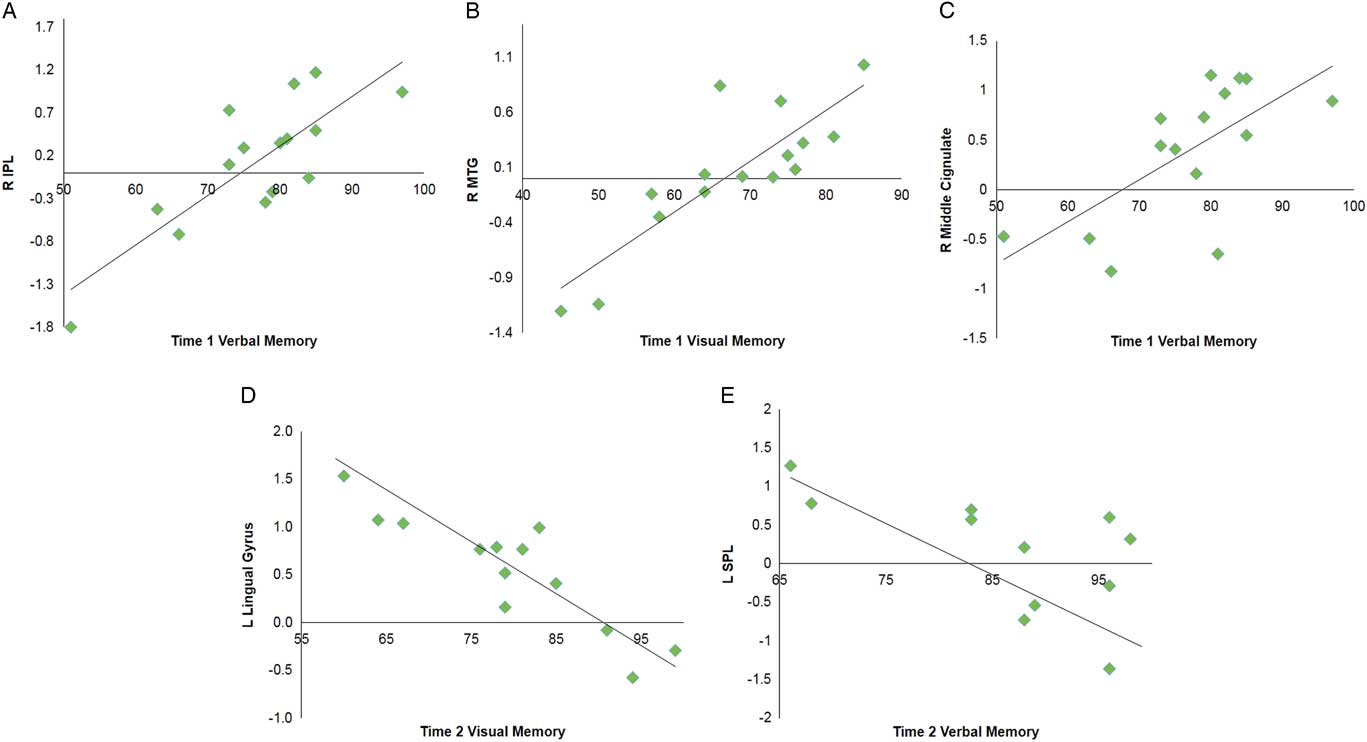

Multiple regression analyses were performed within the SRC group at time 1 and time 2 to assess correlations between functional connectivity and performance on visual and verbal memory composites of the ImPACT. At time 1, significant positive correlations were found between the DMN components and performance on verbal memory for right MCG, postcentral gyrus, and lingual gyrus, and bilateral inferior parietal lobule. A positive relationship was also found for visual memory in the right MTG. No significant negative correlations were seen at time 1. At time 2, a significant negative correlation was with verbal memory for the right vermis, left superior parietal lobule and superior frontal gyrus (SFG). A negative correlation was found with verbal memory for the right IPL. Visual memory at time 2 was also negatively correlated with the DMN components within the left lingual gyrus and right MFG (Table 4; Figure 3).

Fig. 3 Selected graphs showing correlations between select brain regions and verbal and visual memory composite scores on the ImPACT at time 1 (A–C) and time 2 (D,E). In all graphs, y-axis indicates functional connectivity Z scores for the labeled brain region, and x-axis indicates performance score on the labeled ImPACT measure, with higher scores indicative of better performance. R, right hemisphere; L, left hemisphere; IPL, inferior parietal lobule; MTG, middle temporal gyrus; SPL, superior parietal lobule.

Table 4 Multiple regression analyses within the SRC group for time 1 and time 2 separately to assess correlations between DMN component functional connectivity and performance on verbal memory and visual memory composites of the ImPACT

A positive correlation indicates better performance on ImPACT measures is associated with functional connectivity in these brain regions, and negative correlation indicates poorer performance on ImPACT measures is associated with functional connectivity in these brain regions.

L=left hemisphere; R=right hemisphere; BA=Brodmann area; MFG=middle frontal gyrus; MTG=middle temporal gyrus; IPL=inferior parietal lobule; SPL=superior parietal lobule; SFG=superior frontal gyrus.

Memory measures on the ImPACT were most sensitive to differences between adolescents with and without SRC. Particularly noteworthy are the positive correlations between the memory scores and bilateral IPL (including supramarginal gyrus) at time 1. The IPL is a well-known component of the frontal-parietal network involved in sustained attention modulation necessary for working memory (Smith & Jonides, Reference Smith and Jonides1998). Additionally, neuroimaging studies have implicated disruption of IPL in SRC (Jantzen, Anderson, Steinberg, & Kelso, Reference Jantzen, Anderson, Steinberg and Kelso2004; Keightley et al., Reference Keightley, Singh Saluja, Chen, Gagnon, Leonard, Petrides and Ptito2014). Hillary and Grafman (Reference Hillary and Grafman2017) postulate that DMN hubs, of which IPL is a primary hub (the authors use graph theory analyses and refer to hubs as “rich-club nodes”), are functionally hyperconnected to the other network regions after brain injury to overcome network disruption.

While this may be adaptive in the short-term, such as allowing the individuals with SRC to function largely within normal limits, there is likely a trade-off between excessive metabolic demand of these primary “rich-club” hubs and risk of longer-term damage to these regions (Hillary & Grafman, Reference Hillary and Grafman2017). As such, specific to our results, hyperconnectivity of the DMN regions, including IPL, at time 1 suggests an initial compensation for the SRC group to maintain memory performances. Nevertheless, the SRC group continued to remain significantly different from controls with regards to performance at time 1. At time 2, cognitive performance on the ImPACT for the SRC group was not significantly different than controls and behavioral performance in the SRC group had returned to baseline performance. Nevertheless, a positive correlation with IPL remained at time 2, suggesting that the IPL is at risk for chronic hyperactivity as it continues to compensate for network disruption of the DMN. Yet at time 2, negative correlations with both frontal (e.g., SFG, MFG) and posterior (e.g., vermis, lingual gyrus) regions were also seen.

Additionally, results correlating visual-motor coordination and rs-fMRI also fit this pattern, with precuneus, another DMN hub, differentially being recruited at time 1 and time 2. Taken together, these negative correlation findings are consistent with resource allocation theory in that those individuals with increased activity in these regions showed decreased performance on memory measures. Johnson et al. (Reference Johnson, Zhang, Gay, Horovitz, Hallett, Sebastianelli and Slobounov2012) suggested that altered resting state activity post-SRC was related to dysfunction of long-distance connections between frontal and occipital cortices as seen in other neurological and neurodevelopmental clinical populations.

As such, a subsample of our SRC group who continue to have lower performance on memory measures at time 2 may be showing altered allocation of these longer anterior to posterior functional connections. This more nuanced profile of both compensatory mechanisms (activity associated with adequate performance) and resource allocation (activity associated with impaired performance) requires further examination over time, as long-term hyperconnectivity of regions may lead to detrimental hypoconnectivity and more permanent neuropathological changes in the future (Hillary & Grafman, Reference Hillary and Grafman2017).